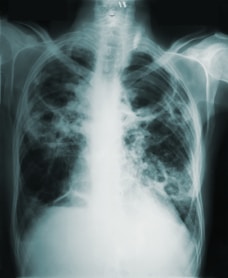

List of Disease